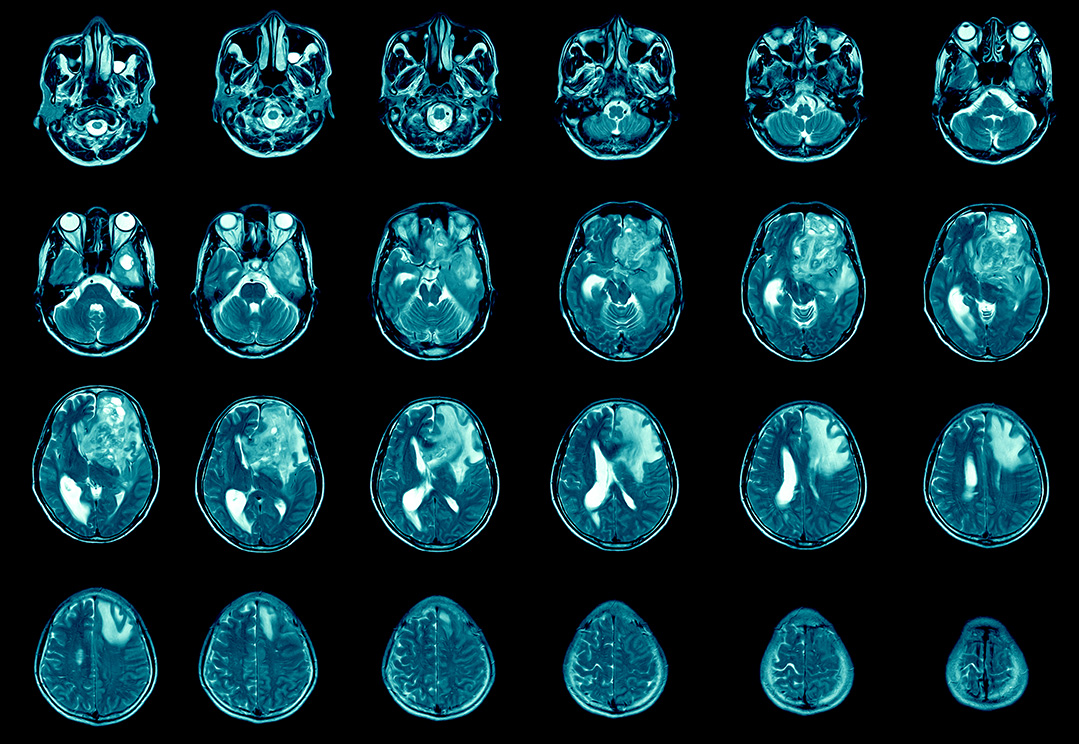

Oct 28 2021 216 PM. How long does end stage glioblastoma last. Glioblastoma is an aggressive type of cancer that can occur in the brain or spinal cord.